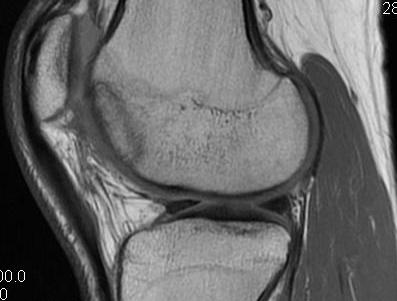

MFC OCD on presentation T2 image 6 months later

T1 sagittal on presentation T1 sagittal six months later